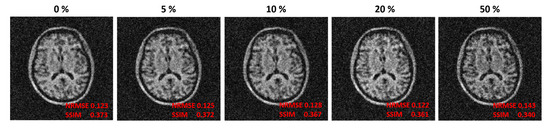

| 0 | 4096 MB | 11,520 MB | 0.7 MB | 15,617 MB |

| 5% | 4096 MB | 338.8 MB | 0.7 MB | 4436 MB |

| 10% | 4096 MB | 170.7 MB | 0.7 MB | 4267 MB |

| 20% | 4096 MB | 84.5 MB | 0.7 MB | 4181 MB |

| 50% | 4096 MB | 45.1 MB | 0.7 MB | 4142 MB |